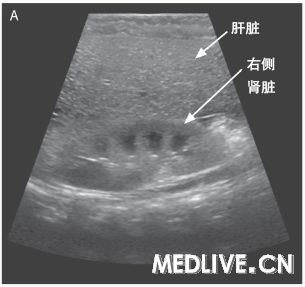

图2 肝活检标本 在低倍放大时(图A),一种小泡型的脂肪变性主要存在于(肝)中央小叶区(箭头),以及大泡型存在于门管区周围(箭)。在较高倍放大时(图B),广泛性小泡性脂肪变性存在于中心小静脉周围肝脏的中央小叶区(箭头)。被膜下区(图C)显示广泛的小泡性脂肪变性(箭头)。超微结构检查(图D)显示一个肝细胞含有不明显的线粒体和非膜结合性脂质囊泡(箭)。

米哈伊尔·利索夫斯基医师:(我们)进行了一次肝脏楔形活检。活检标本显示弥漫性重度脂肪变性(图2A、2B和2C)。小泡性(脂肪变性)形式主要见于小叶中央区,而大泡性(脂肪变性)形式存在于门管周围区域。没有肝炎、肝细胞坏死、纤维化或胆小管反应的证据,并且没有巨线粒体或可极化物质。使用淀粉酶消化的过碘酸-希夫(Schiff)染色显示肝细胞中没有胞浆内小体,并且没有糖原蓄积。铜和铁的染色以及黏多糖的胶体铁染色为阴性。电子显微镜观察证实肝细胞中存在丰富的非膜结合性脂质囊泡(图2D),并且没有显示线粒体异常、糖原沉积或其他的蓄积产物。(我们)做出了弥漫性小泡性和大泡性脂肪变性的诊断。

小泡性脂肪变性由线粒体功能受损导致,在这种情况下,脂肪酸β氧化减少导致三酰甘油(triacylglycerol)和游离脂肪酸的蓄积7。在本例患儿的年龄组中,线粒体功能障碍通常由一种遗传性代谢错误或一种药物或毒素的作用所致8。遗传缺陷可涉及线粒体的氧化磷酸化、脂肪酸氧化或尿素生成系统。门管周围糖原化的核(glycogenated nuclei)、门管纤维化和肝细胞糖原聚集物的缺乏并不支持尿素生成障碍9。与线粒体氧化磷酸化异常相关的胆小管反应和纤维化并未被观察到10。我们考虑到了沃尔曼(Wolman)病(由溶酶体酸性脂酶无活性引起)以及胆固醇酯贮积病(由溶酶体酸性脂酶活性降低引起),但缺乏泡沫样巨噬细胞和库普弗细胞、可极化胆固醇酯晶体、纤维化,以及电子显微镜下没有膜结合性脂质和晶体并不符合这种诊断11。